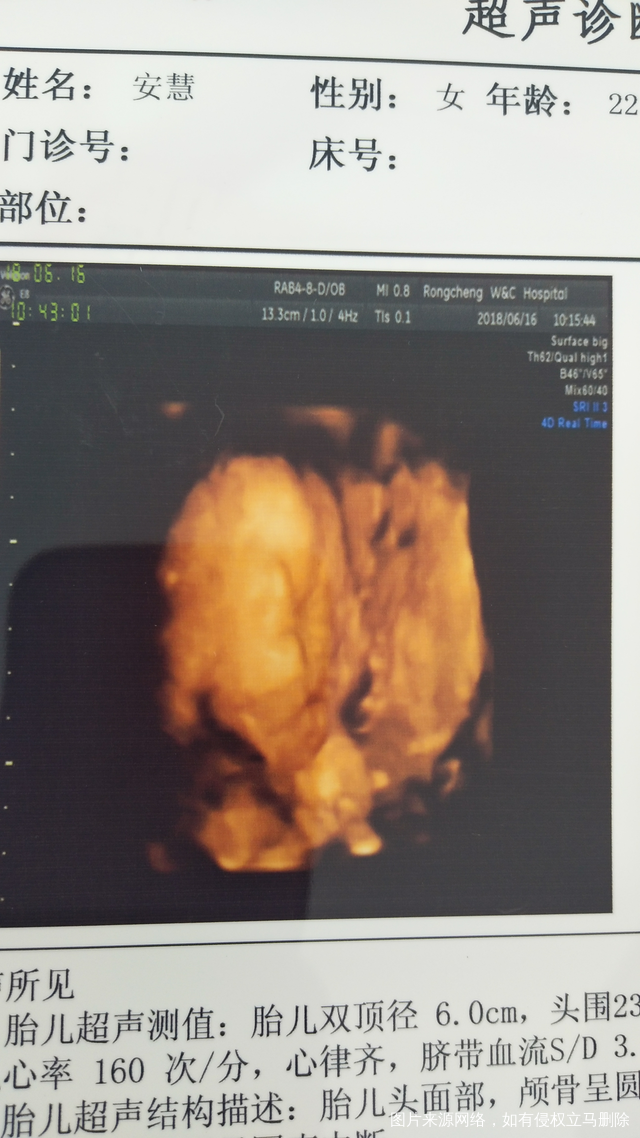

安小慧